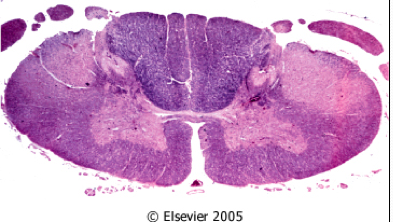

What is shown in the following image?

Huntington disease:

There is loss of neurons (especially small, spiny neurons). Prominent gliosis is present.

What does this image show?

ALS